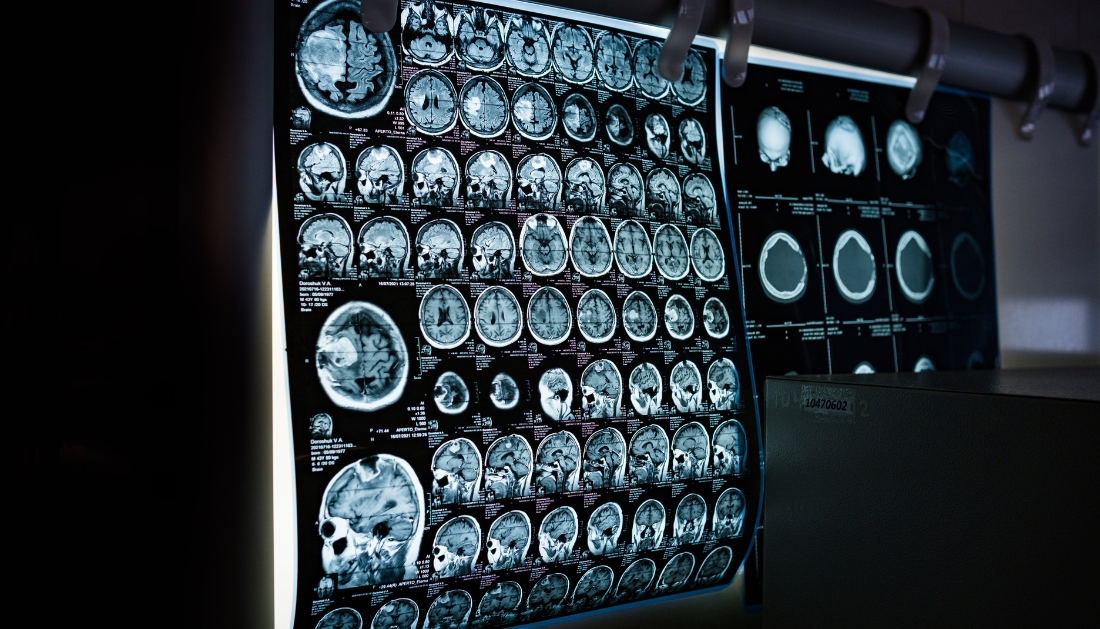

Loberamisal is a dual-target, small-molecule neuroprotective agent designed to preserve neurovascular unit integrity during the early phase of ischemic stroke. Neuroprotective therapies aim to reduce secondary brain injury after vessel occlusion, an area where prior clinical trials have largely fallen short.

- Biomarker and imaging studies to clarify mechanisms of action